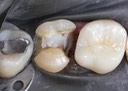

Matt Dodson #30 pre-op